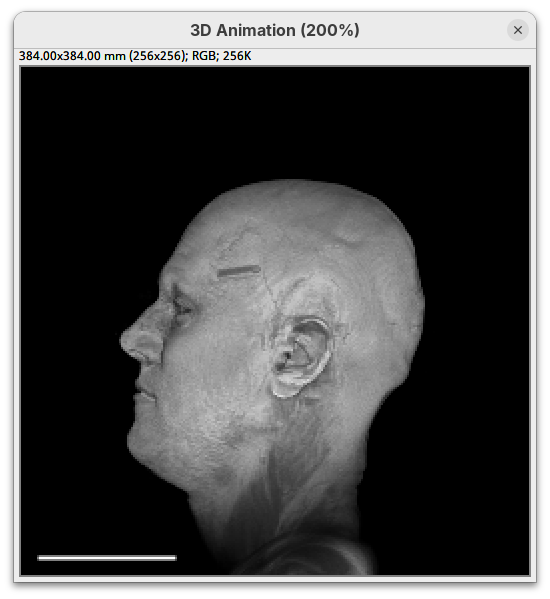

By default 3Dscript sets the gamma value of alpha to 2.0. That’s a good default for fluorescence microscopy (see the next dataset below), but since this is MRI data, we need to tweak it a little differently.

- Set the alpha gamma value to

1.0.

Note that this improves the visualization as the head’s surface becomes better visible.

maxback to500.

Generally, setting the intensity and alpha to the same values is a good starting point for optimizing the rendering.

Transformation

The transformation menu has controls for rotating, translating, and scaling the sample. We can either add values or manually interact with the 3D Animation window to reorient the sample. Let’s try the latter.

- Left-click on the head and move it around.

That’s a great way to see your sample from different angles. And note that the values in the Transformation panel get updated every time you move the sample interactively. In this way you can roughly position the sample and then check and update the precise values for the target transformation.